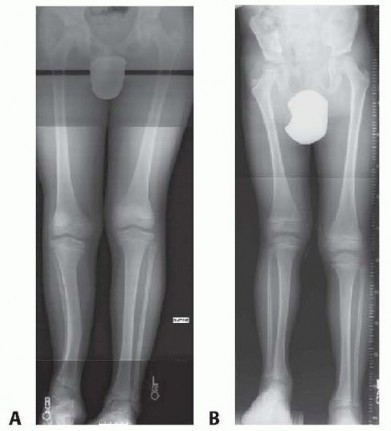

Femoral Rotational Osteotomy (Proximal and Distal) DEFINITIONS Femoral anteversion is the angle in the transv…